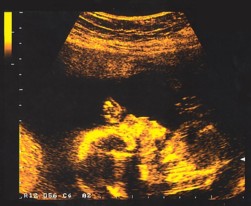

Bébé à 18 semaines

Pour le médecin, les échographies fournissent des informations précieuses sur l’évolution de la grossesse, la croissance de l’embryon…

Le plus émouvant ? Voir battre son coeur !